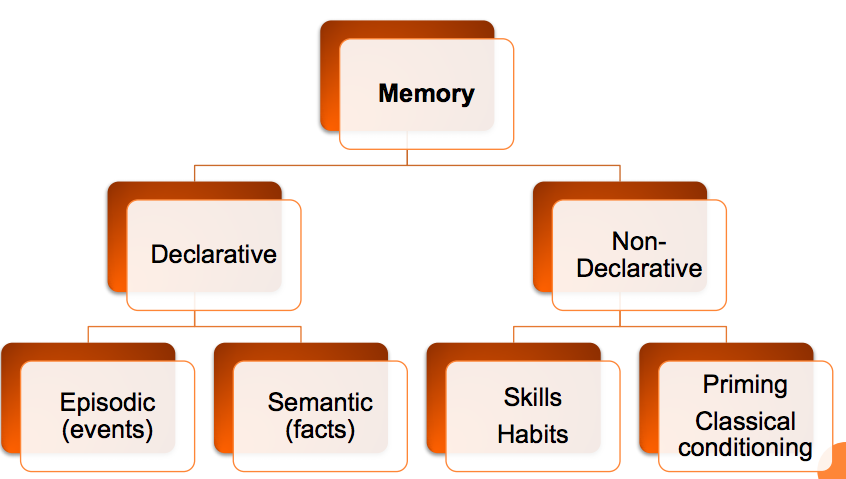

Describe how memory can be broken down into different types?

Describe procedural memory?

Long term, implicit memory

Skill acquisition

Which types of memory typically do or do not break down in disease states?

Non-declarative (procedural) memory typically stays intact

Declarative memory typically breaks down